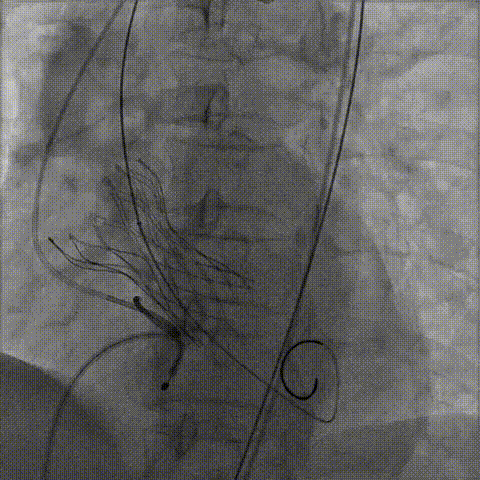

手术影像:

瓣膜膨胀不良

瓣膜膨胀不良进行球囊后扩

球囊后扩后造影无漏